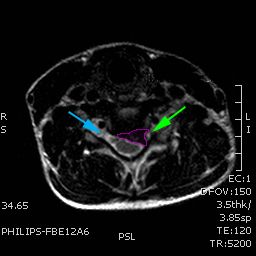

Κήλη αυχενικού δίσκου, επίπεδο Α5-Α6, με στένωση του νευρικού τρήματος (πράσινο βέλος) και πίεση του εξερχόμενου νεύρου. Ελεύθερο τρήμα με κυανό βέλος. |

Ασθενής με αυχενοβραχιόνιο σύνδρομο, κήλη αυχενικού δίσκου με πίεση επί του νεύρου (πράσινο βέλος) |